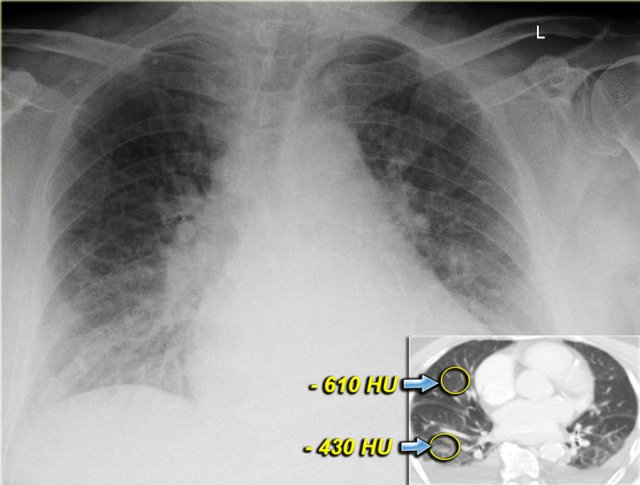

CT will also demonstrate signs of congestive heart failure.

On the image on the left notice the following:

• Thickened septal lines due to interstitial edema

• Subtle ground glass opacity in the dependent part of the lungs (HU difference of 100-150 between the dependent and non-dependent part of the lung).

• Bilateral pleural fluid.

In a patient with a known malignancy lymphangitic carcinomatosis would be high in the differential diagnostic list.

Ground glass opacity is the first presentation of alveolar edema and a precursor of consolidation.